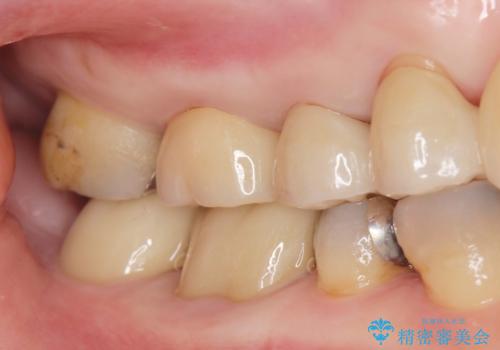

拡大鏡下で虫歯を取り切った後、フルジルコニアクラウンにて治療しました。

適合の良い被せ物が入りました。

メタルの詰め物や被せ物は歯質との間に隙間ができやすく虫歯の原因の細菌が侵入し、虫歯の再発に繋がります。

セラミックの詰め物や被せ物は歯質との間に隙間が出来にくいため虫歯の再発のリスクが低くなります。